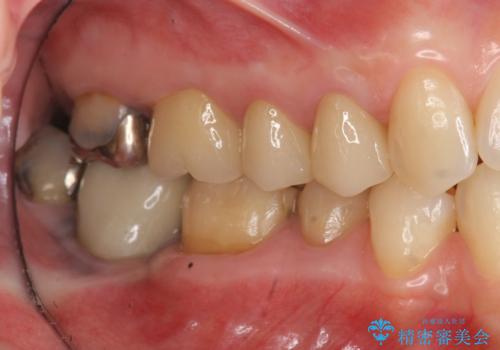

- 歯にものがつまり、以前治療したクラウンの見栄えの悪さの改善を求めて来院されました。

歯ぐきとの境目が、クラウンでしっかりと覆われていないため精密なセラミッククラウンで機能性を回復していきます。

- 40万円(仮歯・ファイバーコア・ジルコニアクラウン×3)費用は治療当時の料金となります

精密なセラミッククラウン製作には、シリコン印象などを用いた精密な型取り、クラウンの製作が大切です。